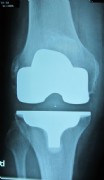

Example of a complete prosthesis

Center left and center right: A modern knee prosthesis with sparing bone removal and sliding surface replacement. Such knee joints are used routinely by us. They are made for the particular patients affected knee.